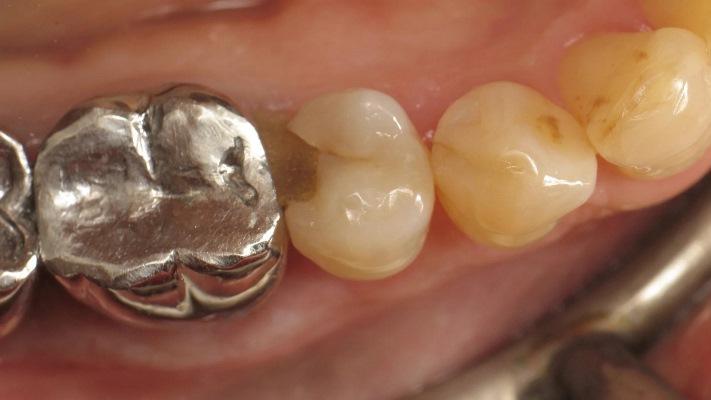

Фото 1. Премоляр с кариесом II класса.